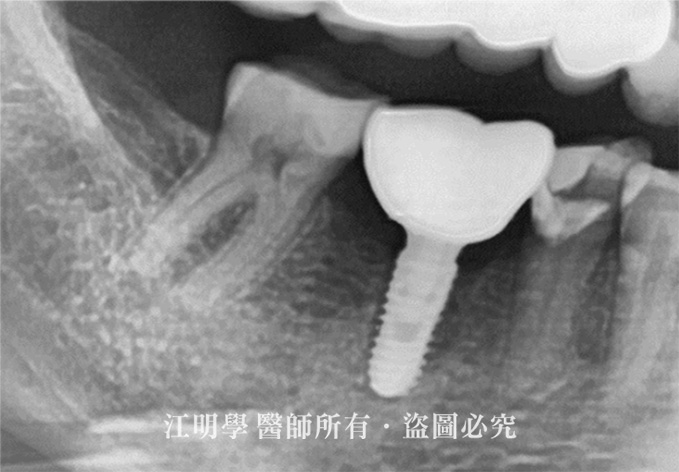

治療後:缺牙處植入植體

治療後X光